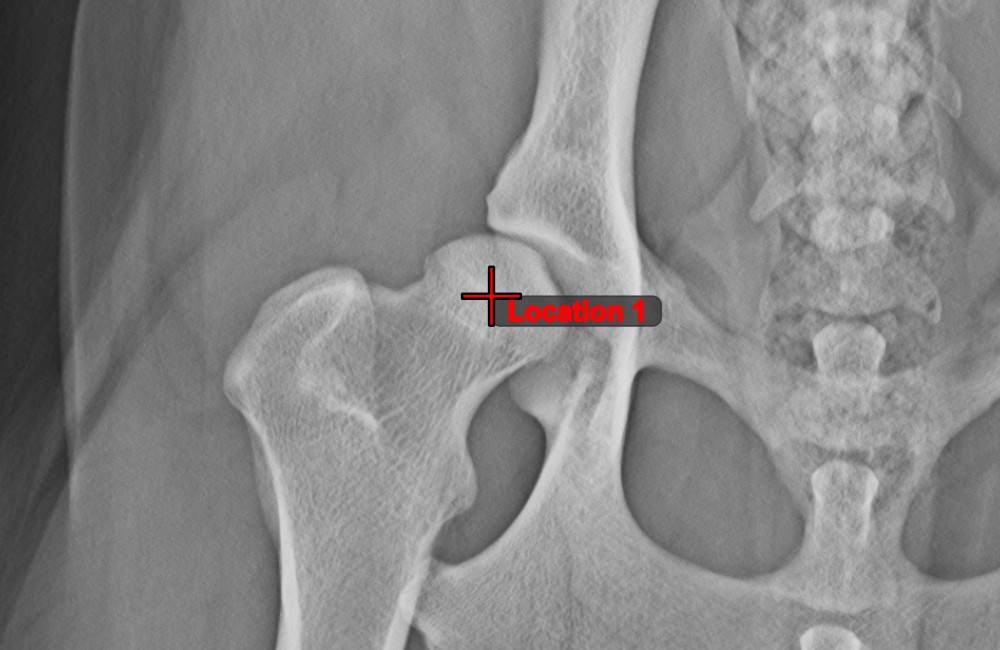

Distance of Line and Point¶

Measure the distance between a line and a specific point on the scene using the Distance of Line and Point tool.

Select the tool from the left toolbar and assign it to one of the available mouse buttons. Start the measurement by selecting an already existing line from the scene. To complete the measurement, place the desired point on the scene or choose from an already exisiting point. The distance between the line and the point will be automatically calculated.

Modify the measurement by moving any of the points using the Select/Move Item tool.